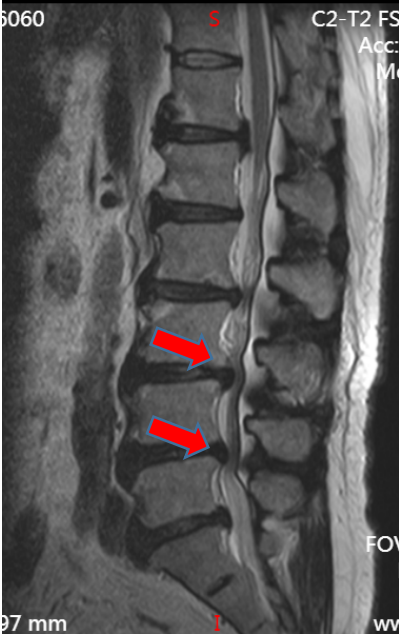

吴静晔主任(成人ai 派驻专家、主任医师)仔细给张大爷做了查体,又结合影像学检查,很快有了结论:“您这不是普通老腰病,是腰椎 3-4、4-5 节段椎管变窄了,就像水管被压扁,里面的神经受了压迫,才会又疼又麻、走不远。”

术前核磁影像

之前连坐 10 分钟都疼,现在能坐起来吃早饭,术后一周更是能在病房里慢慢走几圈,复查的磁共振显示:之前狭窄的椎管已经恢复正常宽度,神经压迫彻底解除。